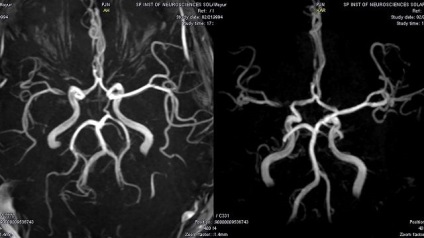

Astăzi tot auzit că există un număr de diagnosticare care permit identificarea oricăror boli. Aceste tipuri de studii includ MRI - imagistica prin rezonanta magnetica. De la descoperirea acestei metode de examinare nu a fost mult timp, dar telefoanele s-au îmbunătățit foarte mult în comparație cu primele modele care vă permite de a vizualiza organele interne și pentru a obține cele mai precise informații.

Această procedură este acum considerată ca fiind cea mai bună soluție pentru diagnosticarea cauzelor bolii, stadiul de dezvoltare, indicând un tratament de succes sau de rafinare diagnostice existente.

În cazul în care pacientul este prescris un RMN cerebral, atunci el ar trebui să înțeleagă care sunt avantajele procedurii. În timpul evenimentului:

calitatea imaginii

Răspunzând la o întrebare despre cât de mult durează diagnostic MR, este necesar să menționăm celelalte caracteristici - ca o fotografie. Dacă IRM cerebral făcut în câteva minute, imaginile sunt de proastă calitate. Are sens pentru a efectua teste de costisitoare, nu pentru a obține informații exacte? Experții spun că ar trebui să îndure atâta timp cât este necesar, și de a obține imagini de înaltă calitate ale creierului, care poate judeca cu adevărat ce au loc procese. Cu alte cuvinte, timpul - un factor important care influențează rezultatul.